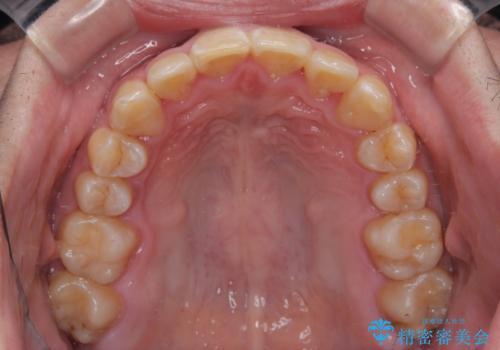

上顎前歯のデコボコを改善してスッキリした口元に ワイヤー装置での非抜歯矯正

- 上顎前歯のデコボコを気にして来院された患者様です。

上下前歯にデコボコがありましたが、特に上顎の叢生が強く、通常に歯列を整えると、上顎が前方に突出し、口元の突出感が残った仕上がりとなる可能性が考えられました。

補助装置を用いて上顎歯列全体を後方に移動させる力をかけ、唇が閉じやすいような仕上がりを目指して、ワイヤー装置にて矯正治療を行うこととしました。